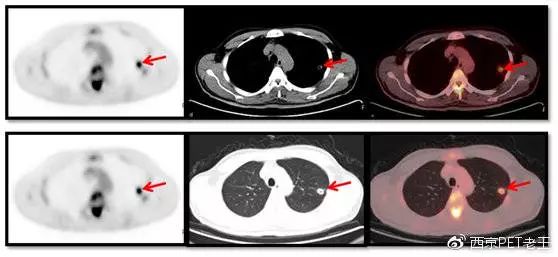

我们又发现了这么多的骨转移病变,那原发病灶究竟在哪里呢?我们仔细寻找,在左肺上叶发现了一个空洞样病变,边缘见细毛刺及胸膜牵拉征,呈葡萄糖代谢异常增高,我们考虑为恶性病变(肺癌?),如下图:

左肺上叶发现了一个空洞样病变(红色)